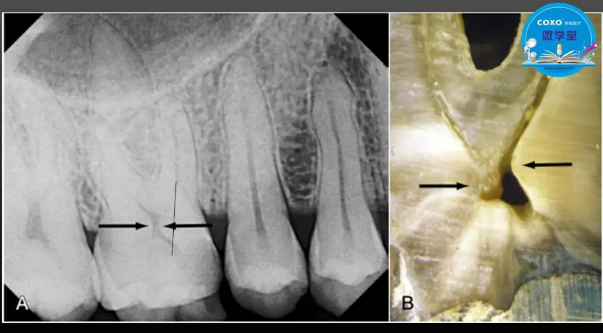

主講:孫書昱

主任醫(yī)師,牙體牙髓副主任, 廣東省口腔醫(yī)院牙體牙髓科 主任醫(yī)師。2003年碩士研究生畢業(yè),研究方向為牙體牙髓病學,擅長于牙體牙髓病的診斷、齲齒、牙髓炎、根尖周病的治療以及前牙美容修復。